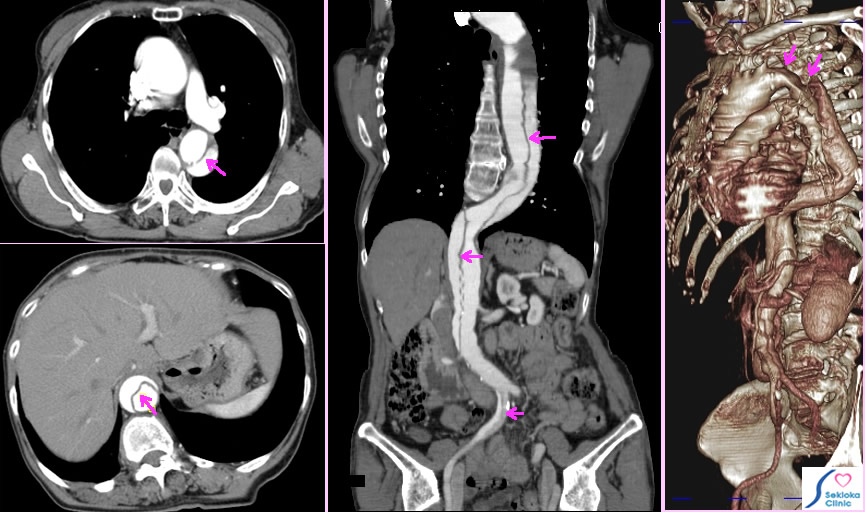

| 診断 | 部位によっては(腹部、胸部上行大動脈など)超音波エコー検査で診断されることもあるが、詳細な病気の広がりを観察するには 造影MDCT検査が最も信頼度は高い。下の例では 矢印に示すごとく、胸部下行大動脈に始まり、右総腸骨動脈まで広範な解離が認められました。 |